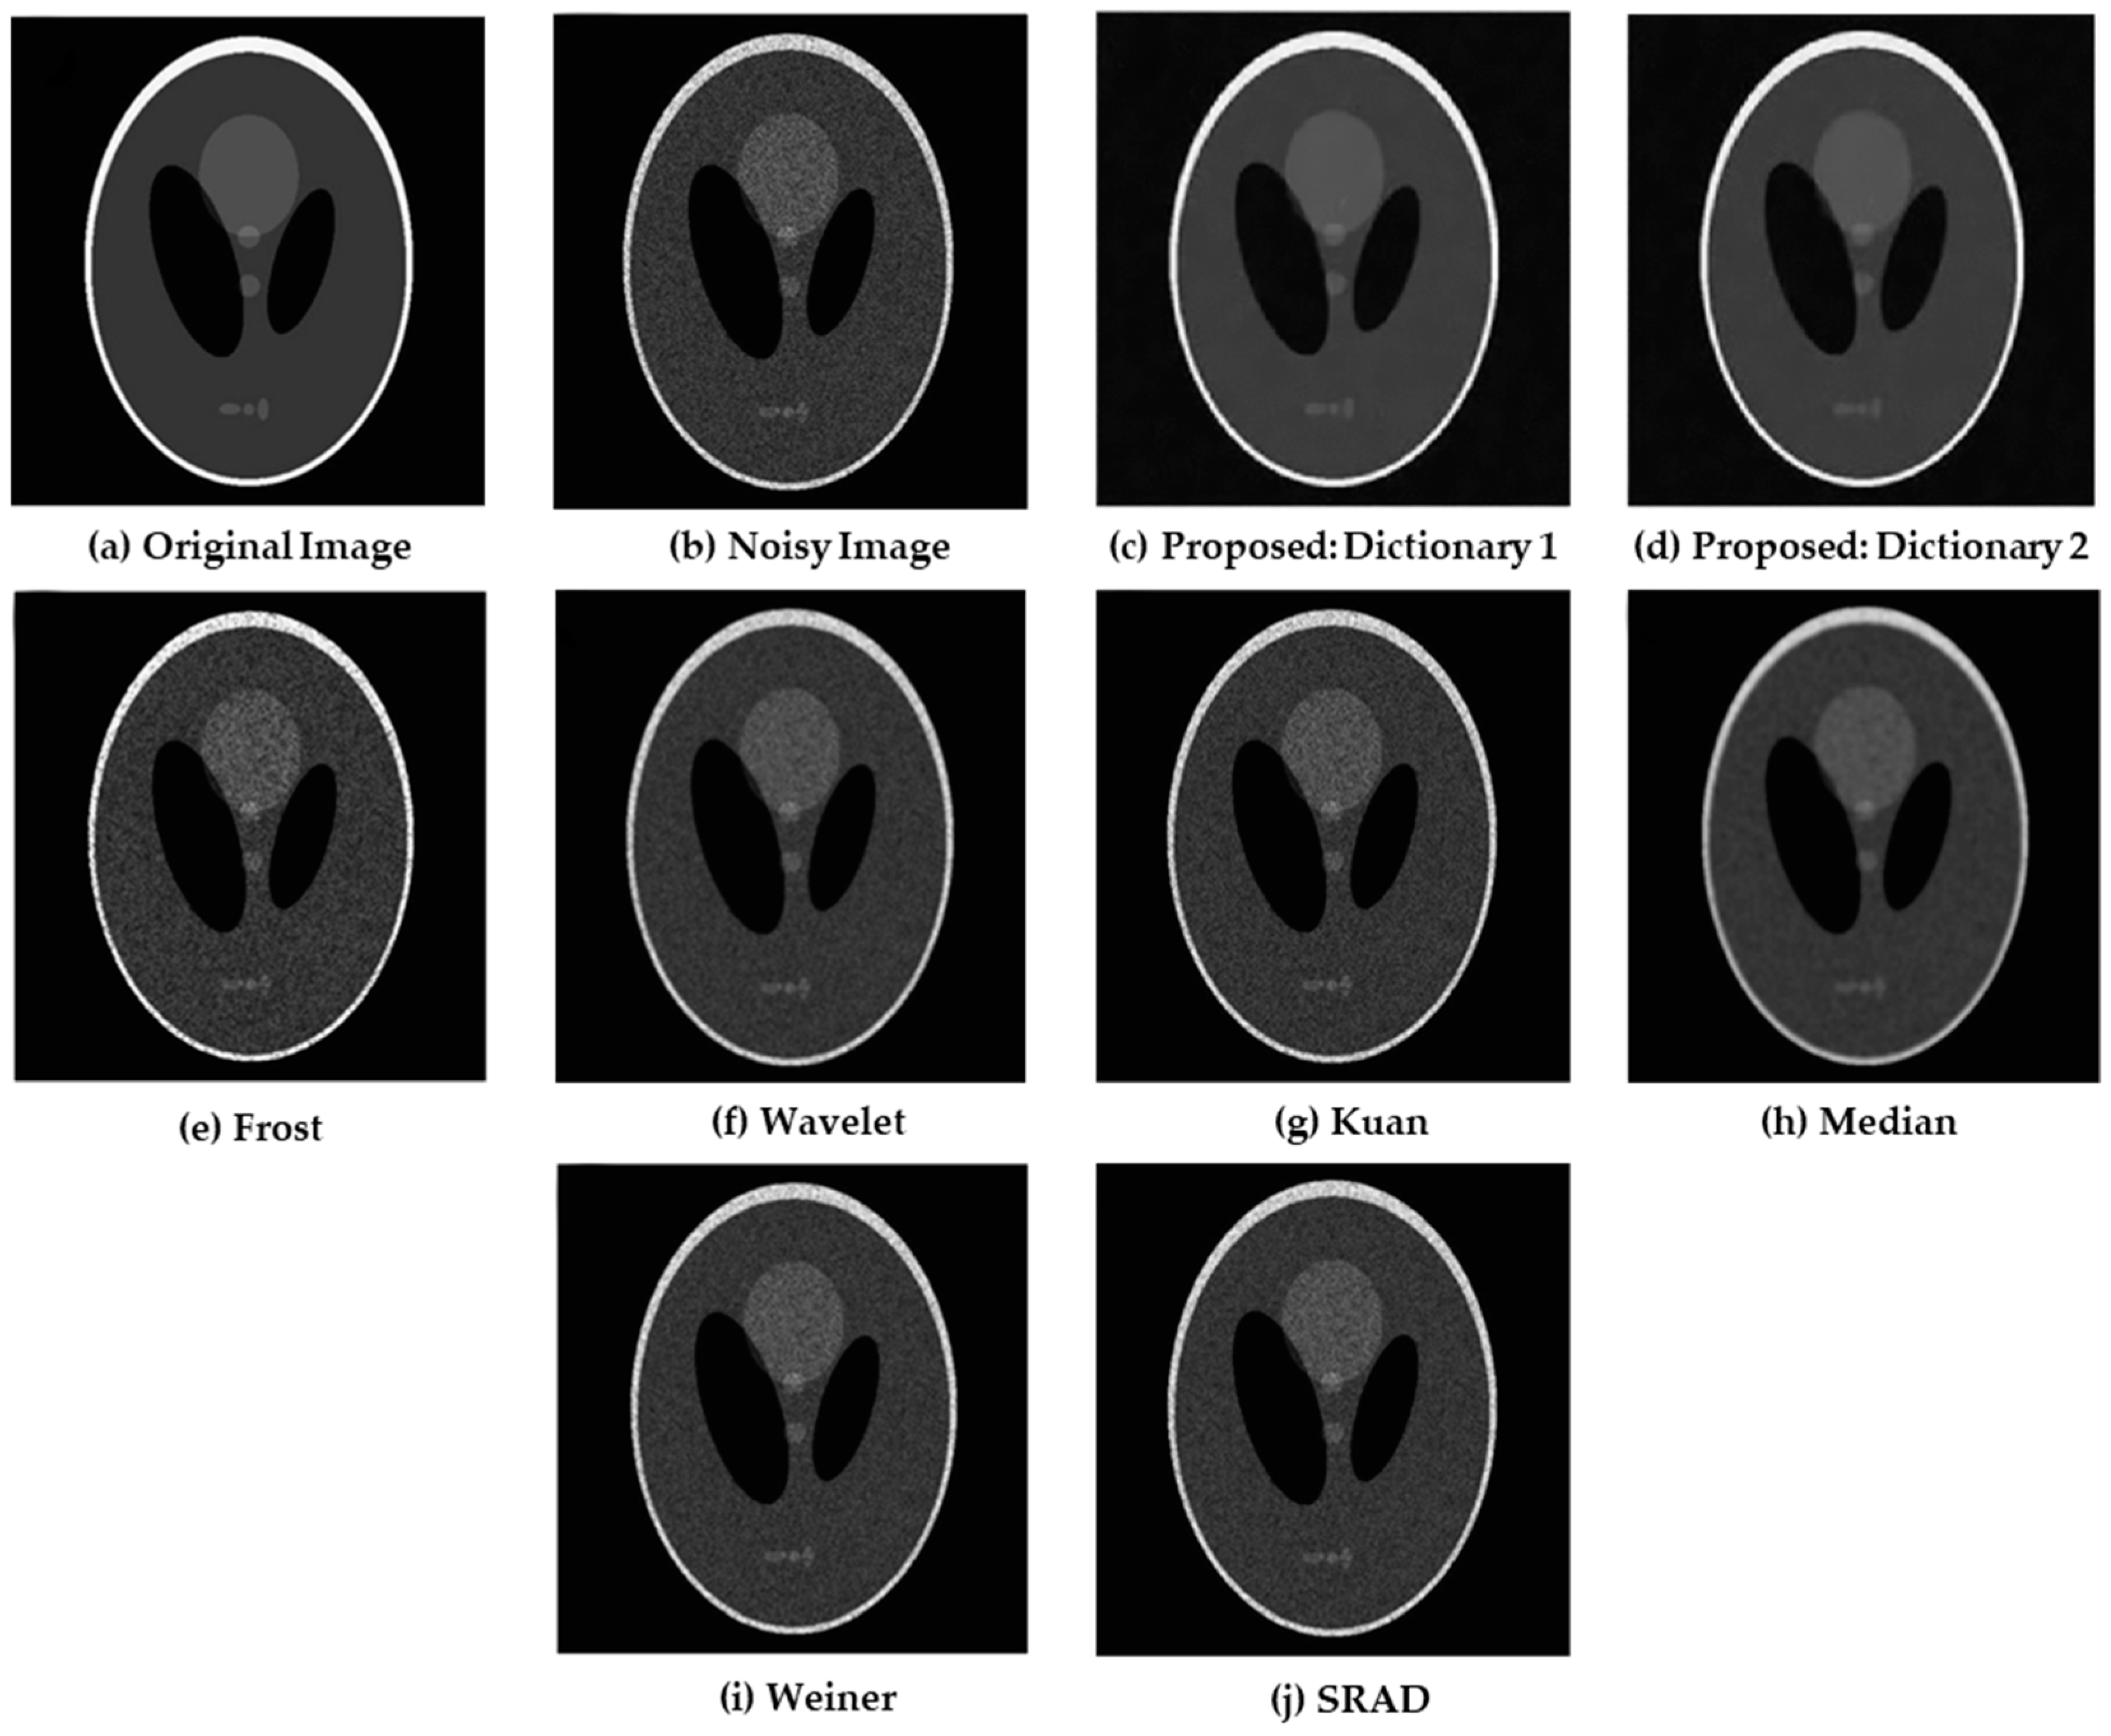

4.1. Simulations on Synthetic Images

| Noise image | 32.113 | 0.727 |

| Frost | 32.466 | 0.768 |

| Wavelet | 33.214 | 0.801 |

| Kuan | 32.895 | 0.794 |

| Median | 34.597 | 0.839 |

| SRAD | 33.434 | 0.827 |

| Weiner | 33.782 | 0.834 |

| Proposed: Dictionary 1 | 36.862 | 0.953 |

| Proposed: Dictionary 2 | 37.044 | 0.967 |